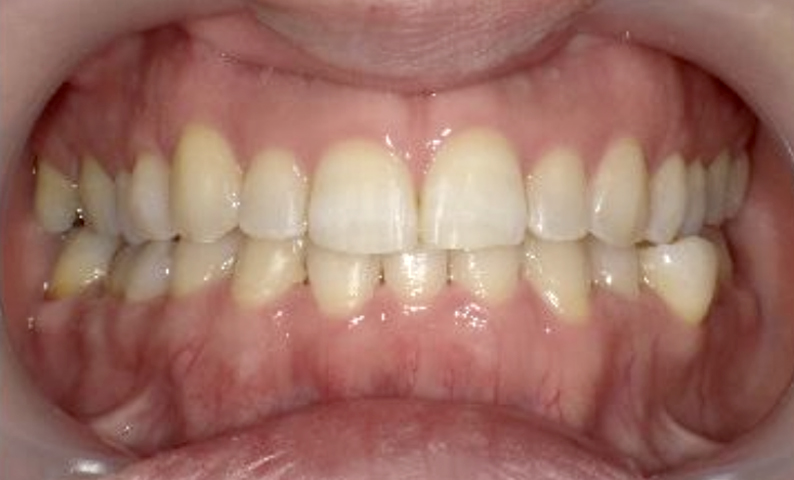

症例_002 上顎だけの部分矯正

治療期間:7ヶ月金額:30万円+税女性前歯のガタガタ上の前歯だけ

| Before | After |

|---|---|

|